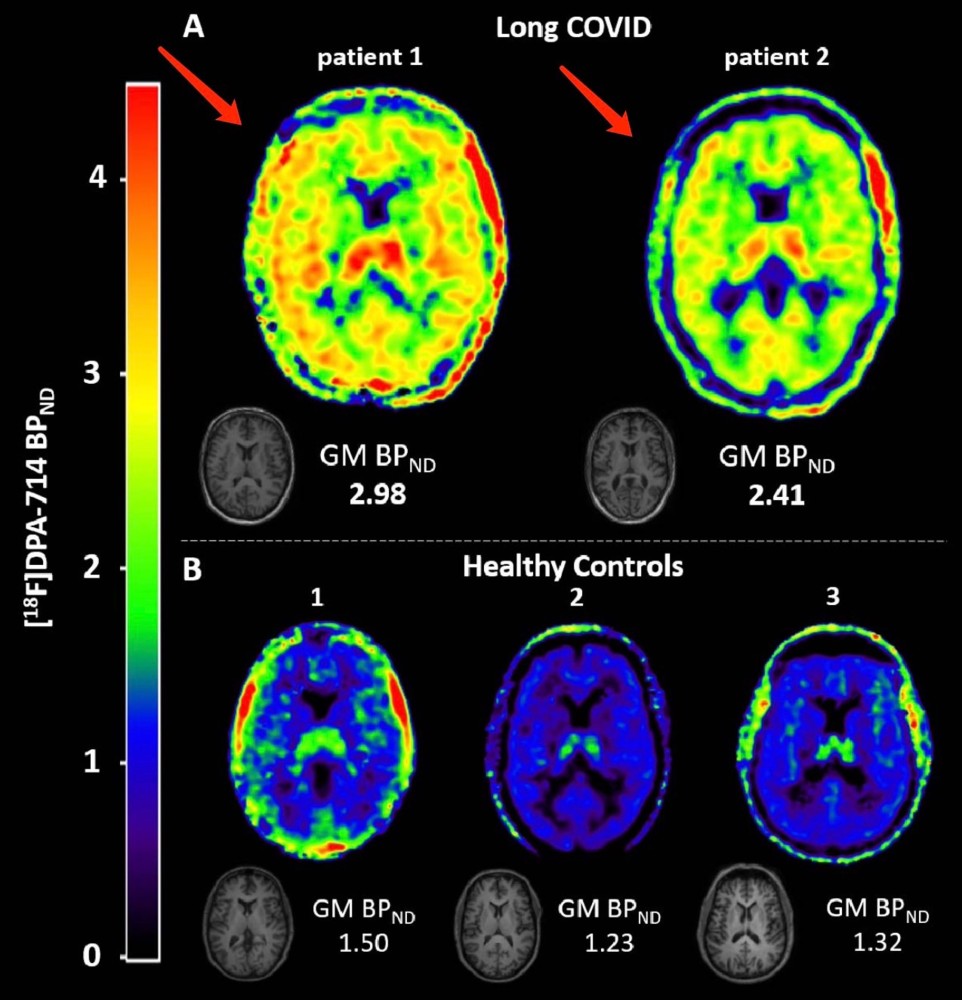

事实上,新冠病毒感染后导致神经系统炎症的报道近来颇受关注。来自荷兰鹿特丹大学医学中心的最新研究显示,长新冠患者的这些症状与大脑神经的炎症水平有关。研究团队跟踪重要的大脑炎症标记物,通过影像学手段证明长新冠患者存在严重的神经炎症。

来自荷兰鹿特丹大学研究团队在论文《Long COVID is associated with extensive in-vivo neuroinflammation on [18F]DPA-714 PET》中写道,尽管在新冠感染的急性期,新冠病毒主要影响呼吸系统,但其长期影响则主要是神经系统。最常报告的症状是疲劳、嗅觉丧失、味觉障碍和认知问题。即使在初始(呼吸道)症状相对较轻的患者中,这些症状也会在感染后持续数月。按照美国CDC的数据,有五分之一的新冠患者出现了长新冠症状。然而,人们对这些使人衰弱的症状及其长期影响的病理生理学知识仍然非常缺乏。

该研究聚焦于小胶质细胞,这是定居在脑内的吞噬细胞,在炎症刺激下,其抗原性增强,形态伸展,功能活跃。有炎症发生时,小胶质细胞能迅速增殖,增加或重新表达MHC抗原,迁移并变化成吞噬细胞样形态(阿米巴样)同时爆发性分泌大量细胞因子和细胞毒性物质。

小胶质细胞在脑内各部分均有分布,在灰质中的数量比在白质中的多5倍。海马、嗅叶和基底神经节的小胶质细胞比丘脑和下丘脑的多,而脑干与小脑中最少。小胶质细胞广泛认为是中枢神经系统内的主要免疫效应器,参与诸如HIV脑病、帕金森病、阿尔兹海默病(老年痴呆症),多发性硬化等人神经系统紊乱疾病。

该研究采用了正电子发射断层扫描(PET)观察了长新冠患者大脑中的[18F]DPA-714水平,从而评估了患者大脑神经中小胶质细胞激活炎症。[18F]DPA-714是PET示踪剂,是一种高亲和力转运体蛋白(TSPO,一种在脑中活化的小胶质细胞和巨噬细胞中表达的线粒体外膜蛋白,作为神经炎症标志物)配体。[18F]DPA-714可用于评估各种神经炎症模型和脑肿瘤模型中的炎症特异性成像。

荷兰鹿特丹大学研究中的第一名长新冠患者是50多岁的荷兰女性,感染前身体健康、全职工作并过着充实的生活。她于2020年12月核酸检测阳性,在感染的急性期,她没有住院,也不需要治疗。自从感染以来,她出现了严重的疲劳、注意力不集中、嗅觉丧失和嗅觉异常、头痛和一些视力问题。她的症状使她无法工作,她症状一直持续至今,也就是感染后15个月。

研究中的第二名长新冠患者一名60多岁的荷兰男性,感染SARS-CoV-2之前身体健康、全职工作。他于2020年3月核酸检测阳性。在SARS-CoV-2感染的急性期,他在护理病房住院了15天。10天后,他因呼吸问题住进重症监护室(ICU),时间为一天。在住院期间,他接受了标准药物治疗。自感染以来,他患有严重的疲劳和注意力不集中,并且无法工作。尽管此后情况有所改善,但他的症状一直持续至今,也就是感染后24个月。

研究者对2名长新冠患者进行了动脉血样动态60分钟[18F]DPA-714PET扫描。为了评估示踪剂代谢,研究者将两名长新冠患者血液中的[18F]DPA-714代谢物与所有其他可用受试者的血液中的代谢物进行了比较。他们评估了全血中的活性浓度,校正了来自动脉血样本的注射活性和示踪母体分数。

研究发现,长新冠患者1在所有脑区的[18F]DPA-714结合严重升高。其2T4k_VB模型获得的全脑灰质定量BPND(=k3/k4)相对于健康对照受试者平均增加了121%。长新冠患者2的[18F]DPA-714结合也升高了,从2T4k_VB模型获得的全脑灰质BPND(=k3/k4)相对于健康对照受试者平均增加79%。